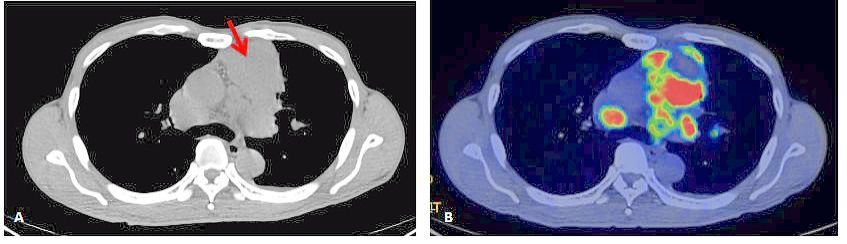

Once administered, the tracer binds to the targeted cells while emitting radiation as a signal.

Specialised imaging devices, such as gamma cameras or PET (positron emission tomography) scanners, then detect this radiation, allowing doctors to pinpoint the tumour’s exact location.

After identifying the tumour, doctors can use a higher-energy therapeutic isotope to deliver targeted radiation and destroy the cancer cells.

This dual approach – using the same tracer for both diagnosis and treatment – is known as theranostics, combining therapy and diagnostics in a single strategy.

A PSMA PET scan enables doctors to detect the cancer with high precision.

“If the disease is identified, a higher-energy radioisotope can then be used to deliver targeted treatment directly to kill the tumour,” he explains.